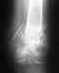

Многооскольчатый перелом голени со смещением. Как мне ускорить процесс заживления? Какие принимать препараты ?Сколько ходить в Илизарове? С момента перелома 2 месяца. Снимок сделан после компрессии. Даю нагрузку 22кг.

По этому снимку не очень хорошо видно, похоже, вовлечена суставная поверхность. Надо делать КТ. Возможно, что-то надо будет еще сделать, если форма суставной поверхности не восстановлена. А есть снимок до наложения аппарата?